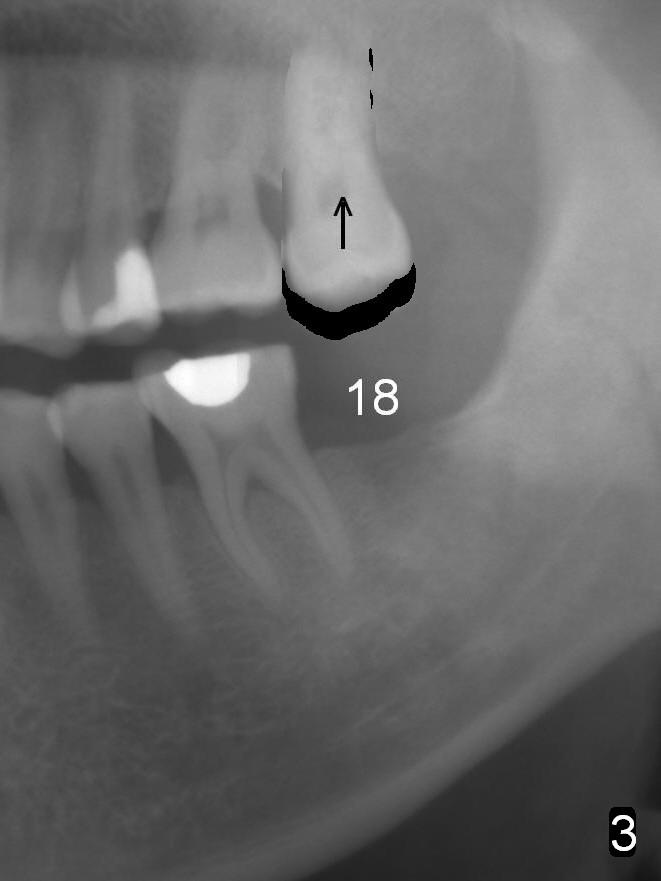

In fact, the tooth 15 had basically no extrusion 6 years earlier (Fig.2) with even occlusal plane. When the tooth is intruded orthodontically, the occlusal plane may be not even (Fig.3). When the implant at #18 osteointegrates (Fig.4 green), fabricate a provisional (grey rectangle) with higher mesial occlusal surface. For certain period of time, the tooth #15 may change its axis so that the mesial portion of the tooth may be intruded more (Fig.5 arrow).